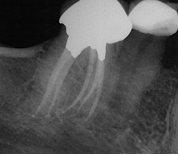

Treatment Examples

Conventional Treatment with Standard Core Restoration

Non-surgical endodontic treatment with resin core build up